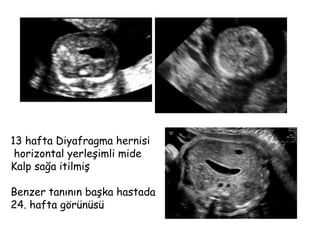

13 hafta Diyafragma hernisi

horizontal yerleşimli mide

Kalp sağa itilmiş

Benzer tanının başka hastada

24. hafta görünüsü